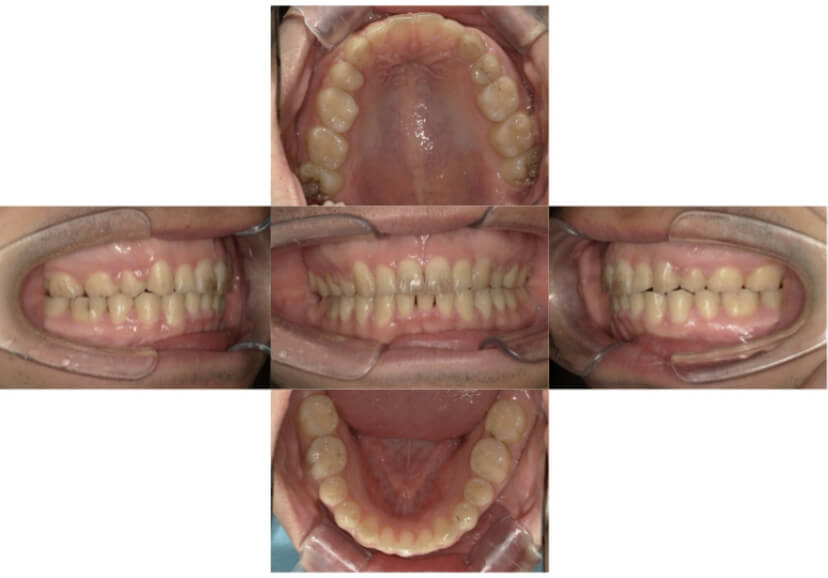

症例1

上顎前突、叢生

抜歯

ブラケット矯正

上下顎叢生、上顎前突(出っ歯、上下の前歯のガタガタ)のケースです。

装置はラビアル(上下表側)で、上顎の小臼歯を2本抜歯を行っています。抜歯したスペースを使って、上の前歯の後方移動と叢生(ガタガタ)と出っ歯の改善を行っています。下は歯と歯の間にIPR(隣接面削合)を行い、スペースを確保し、叢生の改善を行っています。

主訴 前歯のガタガタと出っ歯が気になる。

年齢・性別 47歳 女性

お住まいの地域 神奈川県川崎市

治療方針 抜歯スペースおよびIPRを利用して上前歯の叢生(ガタガタ)の改善

抜歯部位 上顎左右第一小臼歯

使用装置 ラビアル(上下表側)、顎間ゴム

治療期間 2年0か月

治療回数 15回

リテーナー クリアリテーナー

BEFORE

AFTER